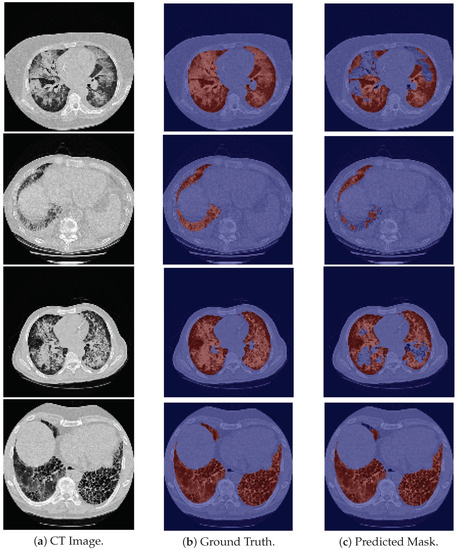

With respect to the 24-LCTSC dataset, the model is generally able to correctly segment the pulmonary images (see the first row in Figure 2), but fails to identify their initial slices, which correspond to the base of the lung, leading to a decrease in the DSC (see the second row in Figure 2). Furthermore, for one of the patients, the masks produced by the model seem to be more accurate than the ground truth images, as the latter excludes part of the lung parenchyma. An example is shown in the third row in Figure 2. Therefore, even though this contributes to a lower DSC due to the discrepancy between them, the predicted mask is more precise. On the other hand, there are cases in which nodules are not included in the ground truth, and there are elements that the model does not include as well, giving rise to a higher DSC, although incorrectly classified. An example is depicted in Figure 2, fourth row.

Figure 2. Examples of LCTSC images, the ground truth and the predicted mask. From top to bottom the examples are, respectively: good segmentation example; an example in which the model fails to segment the base of the lung; an example of a ground truth image that excludes part of the parenchyma of the lung; an example that excludes a nodule in its ground truth, and which is also misclassified by the model.

Applsci 12 01959 g002